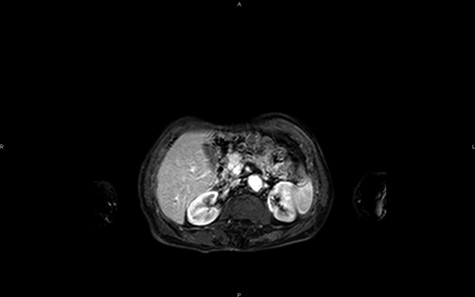

Magnetic resonance imaging (MRI) confirms the hypervascularized and atypical character of this pancreatic tumor (Figs 2 and 3). Moreover, one hepatic lesion with the same characteristics is highlighted.

MRI in axial section, phase T1 + gadolinium: visualization of a structure with hypersignal at the level of the head of the pancreas.